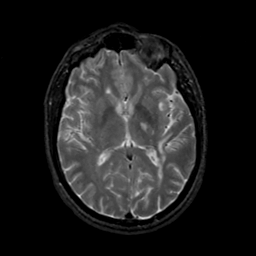

MR Study #19, August 25, 1991 -- Slice #26